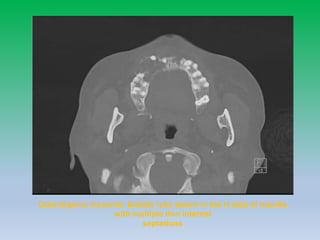

Odontogenic myxoma: Bubbly lytic lesion in the rt side of maxilla

with multiple thin internal

septations